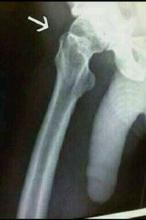

+Anonymous E — 4.8 years ago, 23 minutes later, 2 hours after the original post[T] [B] #617,986

This is when I cracked my hip bone. Didn't break it completely.